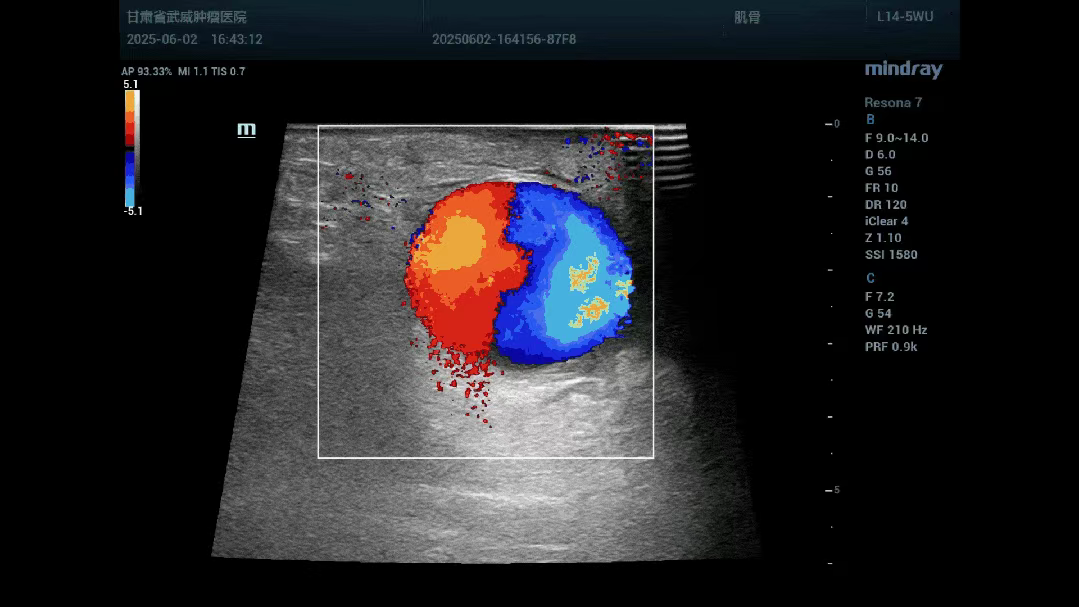

患者朱大妈因进行介入手术后,于右侧股动脉穿刺点形成一假性动脉瘤,大小约5cm左右,加压包扎未能取得良好效果。介入手术很成功,但是穿刺点形成的假性动脉瘤让患者疼痛不适,且右侧腹股沟区皮下形成斑片状青紫区域,进一步增加了朱大妈的心理压力。主管医师通过各种渠道多方咨询,联系到超声医学科寻求帮助。超声医学科通过了解患者病情,检查假性动脉瘤位于右侧股动脉前方,瘤腔大小约48x32mm,与股动脉交通口宽约2mm,内部血流呈旋涡状,彩色血流呈现“太极征”(如图1、2)。与临床医师共同讨论制定治疗方案:在超声实时引导下,向假性动脉瘤内精准注射凝血酶散,促进瘤体内血液凝固迅速形成血栓以堵塞瘤腔(如图3),从而达到治疗目的。超声医学科与主管医师精心做好术前准备,严格按设计流程顺利完成治疗,整个治疗过程约十分钟左右。术后1小时疼痛不适明显减轻,朱大妈十分感谢主管医师为她解决病痛,高高兴兴出院回家了。这就是介入超声的魅力所在,实时精准、方便快捷、疗效肯定,整个治疗过程患者无明显不适,可迅速为临床医师解决棘手问题。

图一:假性动脉瘤“太极图”

图二:瘤腔内旋转血流